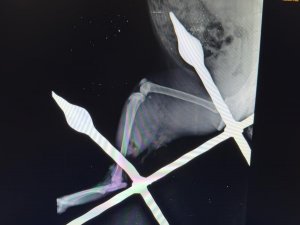

Yaralı kedinin bacağını eski sağlığına kavuşturduklarını anlatan Mersin Büyükşehir Belediyesi Tarımsal Hizmetler Dairesinde Veteriner Hekim olarak görev yapan Yusuf İncir, "Yapılan ilk tespitler sonucunda, balkon demirinin bacağından yaklaşık 10-15 santimetre civarında geçtiği görülmüştür. Yapılan dezenfeksiyon ve temizlik işlemlerinin ardından, balkon demiri anestezi altındaki kedinin bacağından çıkarıldı. Çıkarılırken dokuya mümkün olduğu kadar zarar vermemeye dikkat ettik. Yaptığımız tespitlerde kaslardan bir tanesinin kopmuş olduğu, yalnız sinir dokusunda herhangi bir hasar oluşmadığı tespit edilmiştir. Yapılan yara temizliği ve dezenfeksiyonun ardından, kopan kas kısmı dikişle tekrar eski haline getirildi. Dezenfeksiyonun ardından, yırtılan ve hasar gören dokuların dikiş işlemini gerçekleştirdikten sonra, deri dikişi ile işlemimizi tamamladık. 12 gün zarfında kedimiz sağlığına kavuştu" ifadelerine yer verdi.